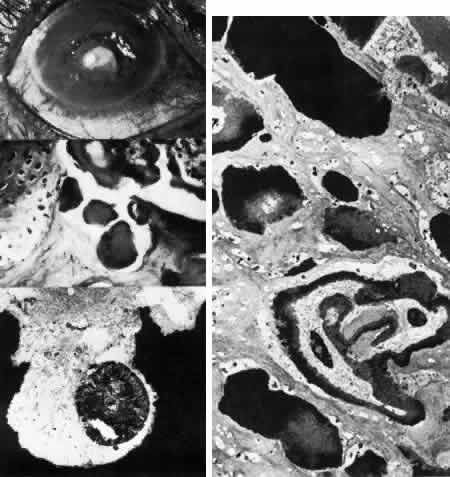

Congenital Hereditary Endothelial Dystrophy

Initially described by Maumenee173 in 1960, this congenital disorder of the endothelium is characterized clinically by diffuse, bilaterally symmetric corneal edema (Figs. 5 AND 15; Color Plate 1J). The autosomal recessive variety is present at birth and is relatively stationary. Symptoms of discomfort are not prominent despite profound epithelial and stromal edema. Nystagmus is common.174 A dominantly inherited form is less severe, developing in the first or second year of life, and, in contrast to the recessive variety, progressive photo(text continues on p. 27) phobia and tearing are the initial symptoms. Nystagmus is generally absent.174 As in all instances of congenital corneal clouding, it is important to rule out congenital glaucoma.

Fig. 15. Congenital hereditary endothelial dystrophy. Top left. Clinical photograph of eye of a 14-year-old male with severe form of the dystrophy shows diffuse ground-glass stromal opacification. Top middle. In a mildly affected 20-year-old female, the cornea has moderate diffuse haze and visual acuity is 20/200. Top right. On slit lamp biomicroscopy, diffuse edematous thickening of the corneal stroma is evident in same patient as top middle photograph. Middle right. Light microscopy of a case with uniformly thickened (approximately 35μm) Descemet's membrane (DM) covered posteriorly by extremely attenuated endothelial cells (arrowheads). S, posterior stroma; AC, anterior chamber (hematoxylin-eosin, × 600). Bottom left. Transmission electron micrograph of same case as middle right micrograph reveals anterior portion of Descemet's membrane (DM) to have normal thickness and banded structure. The markedly thickened (approximately 20 μm) posterior layer exhibits both 55 nm and 110 nm banding (circled) interspersed with homogeneous material. En, endothelial cell; AC, anterior chamber; S, posterior stroma (× 9200). Bottom right. At higher magnification, the abnormal posterior zone is seen to consist of multiple laminations of basement membrane-like material (*) and fine filaments. En, endothelial (× 42,000).

The degree of edematous corneal clouding varies from a mild haze to a milky, ground-glass opacification. Epithelial microbullae may be obvious, and stromal thickness may be increased threefold or more. Uniform thickening of Descemet's membrane is sometimes evident on clinical examination, but no guttata are apparent. Interstitial inflammation and secondary vascularization are absent. There are no definitely associated ocular or systemic abnormalities.

Histologic study175–181 reveals nonspecific anterior and stromal changes consistent with long-standing secondary edema: basal epithelial cell swelling, basement membrane thickening and disruptions, and irregularities of Bowman's layer with pannus formation. However, it may be significant that, in some cases, ultrastructural examination discloses greatly enlarged stromal collagen fibrils sometimes measuring as much as 60 nm in diameter. Descemet's membrane is uniform in a given specimen; it may display diffuse thinning of 3μm to massive thickening of 40 μm (normal thickness is 3 to 5 μm in neonates and 8 to 10 μm in adults). The anterior banded layer of Descemets membrane is always present and of relatively usual thickness; however, the posterior layer consists of multilaminar basement membrane-like material with fine filaments and of collagen fibrils with a 55- and 110-nm banded configuration. With the exception of the lack of guttata, these findings are similar to those in Fuchs' dystrophy and thus represent another example of posterior collagen layer formation by either primarily or secondarily abnormal endothelium.18,41,43,181, It is postulated that in cases with thin Descemet's membrane, complete endothelial loss occurred in utero such that only the fetal anterior portion of Descemet's membrane was secreted.180 In contrast, cases exhibiting thickened Descemet's membranes may be the product of dystrophic but persistent endothelium having secreted a hypertrophic posterior collagen layer.

The frequent finding of enlarged stromal collagen fibrils suggests some primary developmental abnormality of both keratocytes and endothelium, thus perhaps qualifying this disorder as another example of mesenchymal dysgenesis.22